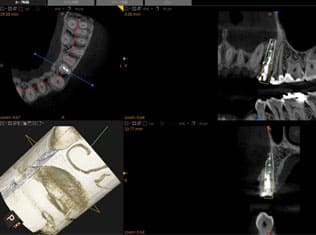

STEP 3

- CT撮影と診断

- インプラントの手術に向けてCTを撮影します。